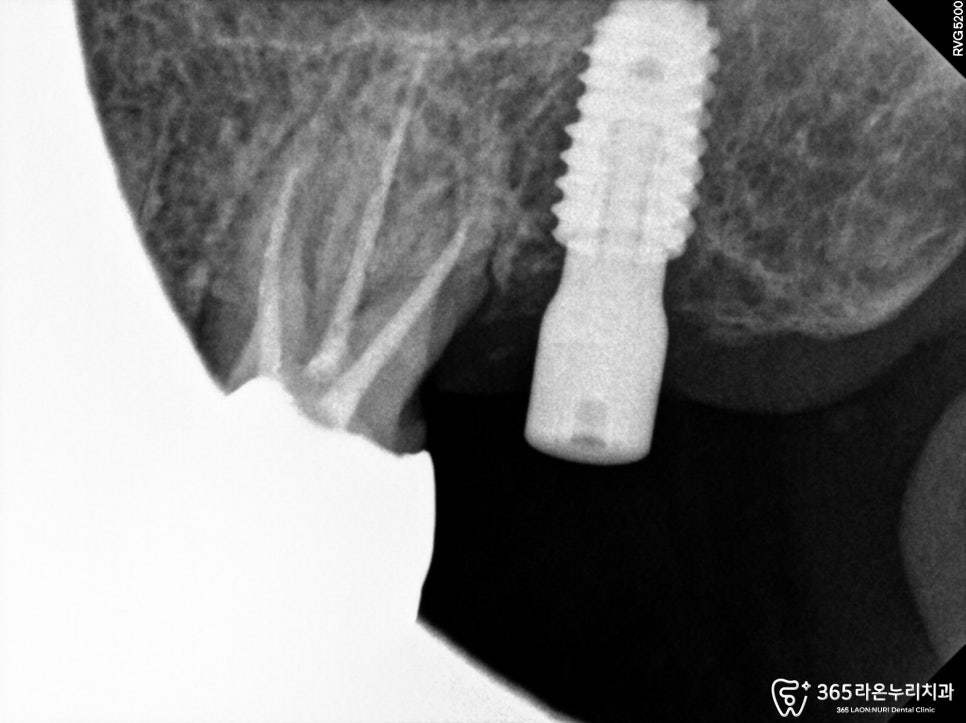

2024. 05. 14

그리고 골유착하는 과정 동안

반대쪽 작은 어금니는

2024. 07. 16

신경치료받는 어금니 가 저작활동 시,

쉽게 깨져버리는 일이 없도록

비워낸 근관에 충전재료를 꽉 채워 넣어드렸습니다.

이후, 임시 보철을 씌워드렸으며

인상채득 과정을 통해

크라운 제작에 들어갔습니다.

그리고 골유착도 완료되면

인상 채득을 해주고,

2024. 10. 11

크라운을 수복해 주고 치료를

마무리 할 수 있는데요.

아무래도 저작 활동을 많이 하며,

저작력을 많이 받는 어금니 였기에

조금 더 튼튼히, 오래 사용할 수 있는

지르코니아 크라운을 사용할 수 있습니다.